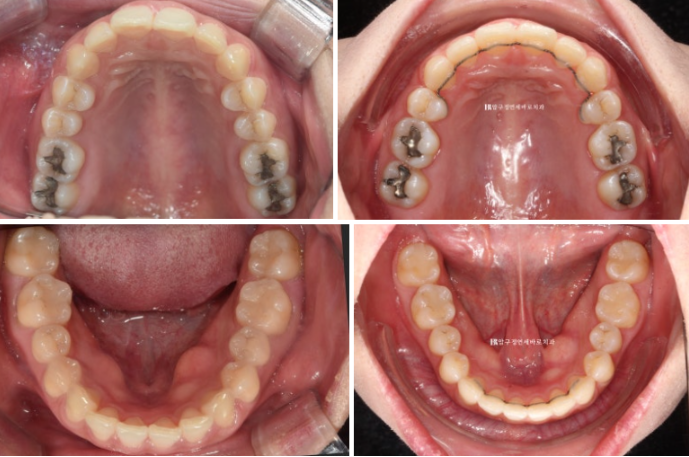

위 작은어금니 두 개를 발치하고 인비절라인 교정 치료에 들어갑니다.

작은어금니를 발치한 지 일주일째가 된 날 인비절라인 첫번째 장치를 끼기 시작한 날 사진입니다.

재제작시 발치공간은 절반정도 남은 상황이였습니다.

24년 7월까지 1년 간 첫번째 추가장치를 다 낀 후 모습입니다.

과개교합은 해결되고 발치공간은 대부분 사라졌지만 여전히 중심선이 미세하게 안 맞고

발치공간에 미세한 틈이 있으며

어금니 교합이 뜨는 부분이 있어서 재제작을 한 번 더 했습니다.

중심선이 잘 맞습니다.

좌 - 치료 전 우 - 치료 후

22.09~24.12

유지장치까지 들어간 모습입니다.